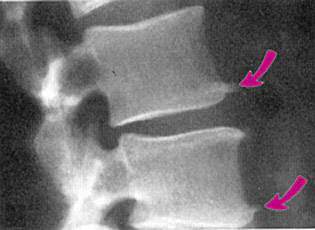

骨刺是脊椎退化過程中所伴隨的一種現象,隨著年齡的增長,人體的脊椎構造也會跟著退化,當骨頭與軟組織接壤的地方因長期承受壓力、拉力、損傷,造成脊椎與脊椎間的軟骨漸漸失去水分與彈性,致使骨骼出現退化性改變,這種骨骼退化性改變就會導致骨質增生,而形成骨刺。另外,反覆活動或不適當的運動,也常會使關節部位的骨骼及軟組織過度磨損,而長出骨刺。骨刺一般好發於活動較頻仍的關節,由於這些關節長時間反覆使用,因此很容易發生磨損與退化的現象。而身體容易誘發骨刺生長的地方包括頸椎、腰椎、膝關節、腳跟,另外,手指跟手肘也是骨刺容易發生的部位。

其實骨刺不見得一定會產生症狀,要看是否有壓迫到神經根或是脊椎,如果沒有的話就不會有什麼讓人不適的症狀產生。相反的,如果骨刺剛好壓迫到附近的神經根或是壓迫到脊椎,就可能會有身體僵硬不能靈活彎身、疼痛、紅腫、麻痺、關節變形、肌肉無力等症狀。發生骨刺可能出現的三種情況:第一種是沒有任何症狀。許多人是因為有其他病症,在接受X光檢查時才發現「骨刺」;這種現象顯示,關節軟骨已發生某種程度的損傷,而身體已作了相當的修補。第二種情況是,局部關節會感到疼痛,出現發炎的症狀或功能異常。這往往是關節炎本身變化所引起,而不完全是骨刺之過。第三種則是骨刺引起了併發症,例如在它附近的軟組織,尤其是神經,受到刺激或壓迫時,會使病人疼痛難當。併發症的程度及嚴重性,完全因受壓迫的部位而異。